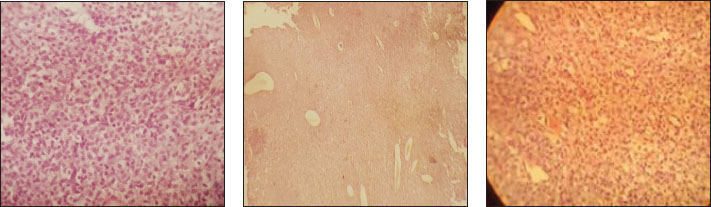

Fig. 4. Gross images after the surgical procedure showing good healing and at least tissue damage. Widespread antibiotics (Cefazolin 20 mg.kg-1 q24 hours) and analgesics (Tramadol 2 mg.kg-1) were administered to prevent infection and control pain management. Sections of the mass reveal a well-circumscribed region composed of sheets of round to polygonal histiocytic cells. The cells exhibit moderate amounts of pale eosinophilic cytoplasm and centrally to eccentrically located round to oval nuclei with finely stippled chromatin and indistinct nucleoli. A mild to moderate infiltrate of small lymphocytes is often observed at the periphery of the lesion (Fig. 5).

Fig. 5. The cells exhibit moderate amounts of pale eosinophilic cytoplasm and centrally to eccentrically located round to oval nuclei with finely stippled chromatin and indistinct nucleoli. DiscussionThis case report highlights the importance of a comprehensive diagnostic approach for an extended, cutaneous histiocytoma. The combination of cytologic, radiologic, and pathologic investigations allowed for an accurate diagnosis of the tumor and its invasion. Early recognition and treatment can improve outcomes for affected animals. Cutaneous histiocytoma is a rare neoplasm that accounts for only 0.3% of all canine skin tumors (Perez-Alenza, 2016; Hohenhaus et al., 2016). The clinical presentation of this case was consistent with that of previous studies, with a rapid growth pattern and painless development (Moore, 2015). The cytologic and pathologic features were also consistent with the diagnosis of histiocytoma. Surgical excision is usually recommended as the primary treatment modality due to the tumor's benign behavior and lack of evidence of metastasis (Vail DM Thamm and Liptak, 2019). In this case, cause of tumor invasion into the maxillary bone, nasal sinus destruction, orbital pressure, ocular discharge, and visual problems, surgical intervention was extremely recommended and radically performed. Several studies have reported cases of cutaneous histiocytoma in dogs, with a predilection in young animals and a benign clinical course. Treatment typically involves surgical excision, although spontaneous regression has been reported in some cases (Palus et al., 2014). The authors believe that any manipulation of the histiocytoma could accelerate tumor development and growth. This case had two time manipulations before surgery, and each manipulation changed most mass. Histopathologic examination of the excised tumor confirmed the presence of histiocytic cells with distinct cytoplasmic features, further supporting the diagnosis of cutaneous histiocytoma. ConclusionOverall, this case report of a massive cutaneous histiocytoma in a 12-year-old intact female dog highlights the importance of considering this benign tumor in the differential diagnosis of cutaneous masses in dogs. Further research is needed to better understand the underlying pathogenesis and behavior of histiocytoma in dogs. The authors believe that although the cutaneous histiocytoma is benign, the distance of the skin to underneath structures could be affected, thereby endangering the prognosis of treatment. AcknowledgmentsThe authors thank Dr. Hassanzadeh Specialized Veterinary Hospital for their kind support. Conflict of interestThe authors declare that they have no conflicts of interest. All data relevant to the study are included in the article. FundingThere was no specific grant for this research from any funding agency in the public, commercial, or not-for-profit sectors. Author’s contributionRN: draft editing, manuscript writing, surgical procedures, methodology, investigation, supervision, data curation. MNN: formal analysis, investigation, software, data curation. AAT: validation, review, editing, visualization. SS: writing, supervision, resources, and conceptualization. MAM: methodology, data curation, software. MR: visualization, validation, investigation, writing draft, resources. MT: validation, review and editing, visualization. AA: formal analysis, investigation, software, data curation. Data availabilityThe authors have no conflict with data availability. The authors have nothing to disclose. No AI-assisted technologies were used in the generation of this manuscript. ReferencesBenaduce Emanuelli Mello, C., Engelmann, A.M., Kommers, G.D., Martins Flores, M., Almeida Fighera, R., Rodrigues E Rodrigues, B., Ceolin Lamego, E., Bagolin Da Silva, C., Bueno, A. and Melazzo De Andrade, C. 2023. Fine needle aspiration cytology: high accuracy in diagnosing cutaneous and subcutaneous neoplasms in dogs. Comp. Clin. Pathol. 32(1), 155–164. Costa, D., Ferreira, R., Prada, J., Queiroga, F.L., Rodrigues, P., Silva, F. and Pires, I. 2020. A role for angiogenesis in canine cutaneous histiocytoma regression: insights into an old clinical enigma. Vivo 34, 3279–3284. García-Reynoso, I.C., Flores-Dueñas, C.A., Castro-del Campo, N., Jácome-Ibarra, M., Herrera-Ramírez, J.C., Gómez-Gómez, S.D., Rodríguez-Gaxiola, M.A. and Gaxiola-Camacho, S.M. 2025. Risk factors for the occurrence of cutaneous neoplasms in dogs: a retrospective study by cytology reports, 2019–2021. Animals 14(15), 2069. Goldschmidt, M.H. and Goldschmidt, K.H. 2018. Canine and feline skin tumors: a review. J. Vet. Dermatol. 29(2), 139–151. Goldstein, R.E., Stoyanov, M.A., Hargis, J.D., Temin, C.W. and DeBey, A.L. 2020. Clinical features and diagnostic imaging findings in dogs with cutaneous histiocytoma: a retrospective study of 54 cases. J. Vet. Inter. Med. 34(3), 847–854. Gualtieri, M., Marogna, G. and Vannozzi, I. 2018. Cutaneous histiocytoma in dogs: a retrospective study of 20 cases. J. Vet. Dermatol. 28(3), 246–253. Hohenhaus, A.E., Kelsey, J.L., Haddad, J., Barber, L., Palmisano, M., Farrelly, J. and Soucy, A. 2016. Canine cutaneous and subcutaneous soft tissue sarcoma: an evidence-based review of case management. J. Am. Anim. Hosp. Assoc. 52(2), 77 -89. Jeong Y.K., Lee, K.C. and Lee, H.B. 2020. CT findings in canine cutaneous histiocytoma: a study of 20 cases. J. Vet. Med. Sci. 82(6), 931–938. Kalosy, K.S., Keating, M.K., Rosenkrantz, W.S. and Moore, P.F. 2025. retrospective evaluation of clonality in canine erythema multiforme. Vet. Dermatol. 1–11. Mariani, C.L., Jennings, M.K., Olby, N.J., Borst, L.B., Brown Jr, J.C., Robertson, I.D., Seiler, G.S. and MacKillop, E. 2015. Histiocytic sarcoma with central nervous system involvement in dogs: 19 cases. J. Vet. Int. Med. 29(2), 607–613. McCue, D.A., Sibley, J.A., Schleis, S.E. and Kiupel, M. 2019. Canine cutaneous histiocytoma: a retrospective study of 114 cases. J. Vet. Inter. Med. 33(4), 1245–1252. Moore, P.F. 2015. A review of histiocytic diseases of dogs and cats. Vet. Pathol. 51(1), 167–184. Olaifa, O.S., Ohore, O.G., Ola, O.O., Usman, A.A., Antia, R.E., Jarikre, T.A., Tijani, M.O., Akinleye, A.O., Oyesiji, E.A., Ajumobi, F. and Oluwarore, K. 2025. Cytopathological comparison of well and poorly differentiated canine soft tissue sarcomas (Fibrosarcomas): diagnostic challenges in a resource-limited setting. Ukrainian J. Vet. Agricult. Sci. 2(82), 70–75. Palus, V., Guillermo, R.M. and Camus, A.C. 2014. Concurrent histiocytoma and mastocytoma in a young dog: case report. BMC. Vet. Res. 12(10), 102. Patterson, A.P. 2020. Pathological features of canine cutaneous histiocytoma a study of 25 cases. J. Comp. Pathol. 182, 19–27. Petal, T.S. 2020. Immunohistochemical characterization of canine cutaneous histiocytoma a study of 25 cases. J. Comp. Pathol. 182, 28–35. Pires, I., Rodrigues, P., Alves, A., Silva, F. and Lopes, C. 2024. Histopathological and ultrastructural study of a canine langerhans cell tumour (canine cutaneous histiocytoma). Cells 13(15), 1263. Ryan, S., Wouters, E.G.H., Nimwegen, S.V. and Kirpensteijn, J. 2022. Skin and subcutaneous tumors. Vet. Surgical Oncol. 29, 92–142. Vail, D.M.T. and Liptak, J.M. 2019. Withrow and MacEwen's small animal clinical oncology: a review of the literature. J. Am. Anim. Hosp. Assoc. 55(2), 93–102. Von Rueden, S.K. and Fan, T.M. 2021. Cancer-immunity cycle and therapeutic interventions-opportunities for including pet dogs with cancer. Front. Oncol. 11, 773420. Wang, Y., Huang, Y., Cai, W.X. and Tao, Q. 2022. Multiple benign fibrous histiocytomas of the mandible: a case report and review of the literature. Exp. Therap. Med. 24(3), 593. | ||